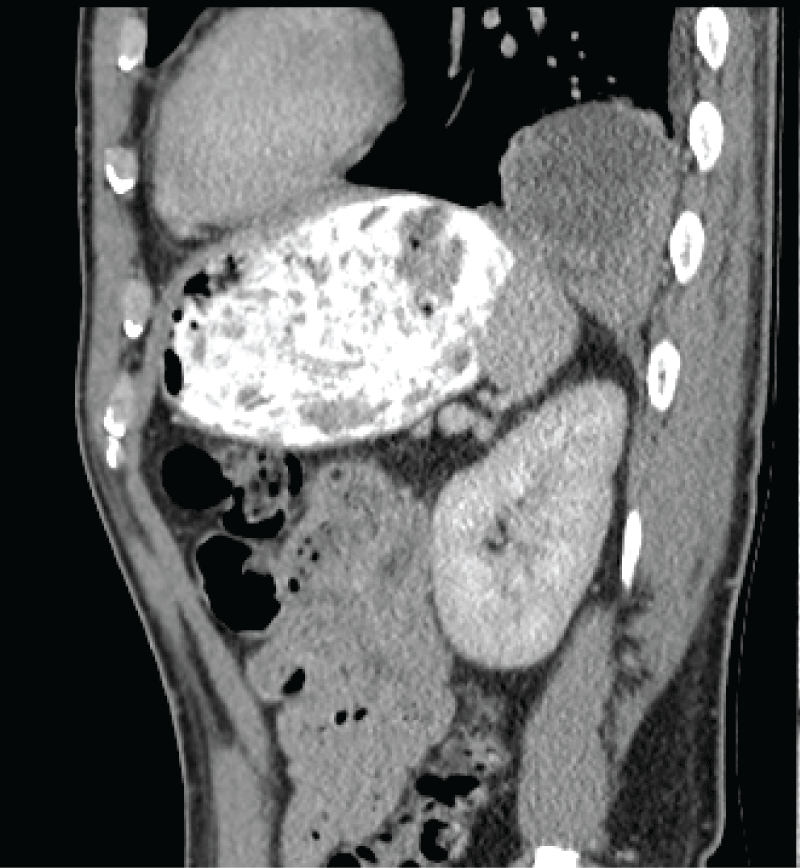

His urinalysis was normal and he had a white blood cell count of twenty, other routine bloods including urea and electrolytes, liver function tests, and lipase were unremarkable however. He went on to have an abdominal CT scan which extended to the lung bases and showed an unusual lesion sitting just above the diaphragm on the left side. Although at first glance similar in appearance to a diaphragmatic, the diaphragm appeared to be intact on the CT scan with no obvious extension of cystic contents below the diaphragm. The lesion was radio dense in appearance and sitting within the posterior basal left lower lobe measuring 94 by 56 mm in diameter. It had low density regions suggestive of fluid or necrosis. There was some associated atelectasis but no pleural effusion. There was no aberrant venous or arterial supply (Figure 1 and Figure 2).